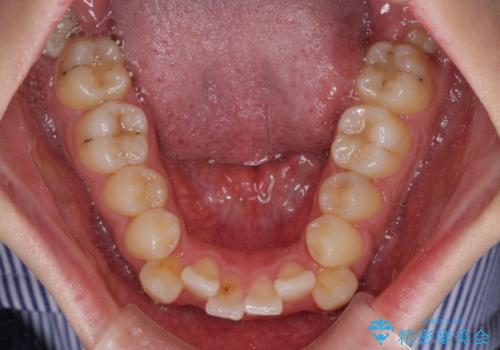

上下の八重歯とクロスバイト ワイヤー装置での抜歯矯正

- 八重歯とクロスバイトを気にして来院された患者様です。

上下ともに八重歯が顕著であり、前歯のクロスバイトがあったため、上下左右の第一小臼歯4本を抜歯し、ワイヤー装置での抜歯矯正を行うこととしました。